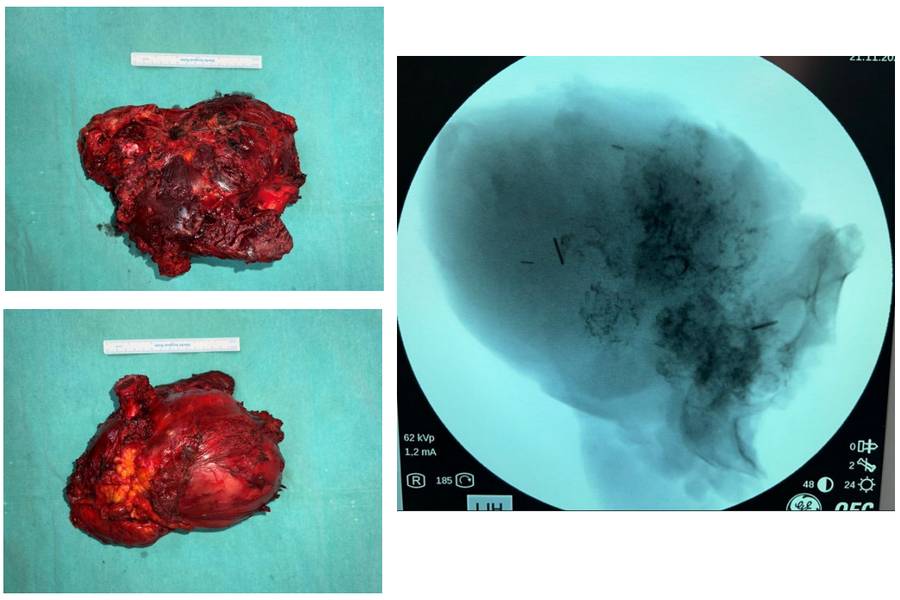

During the Surgery: Clinical and fluoroscopy images of the removed tumor tissue.